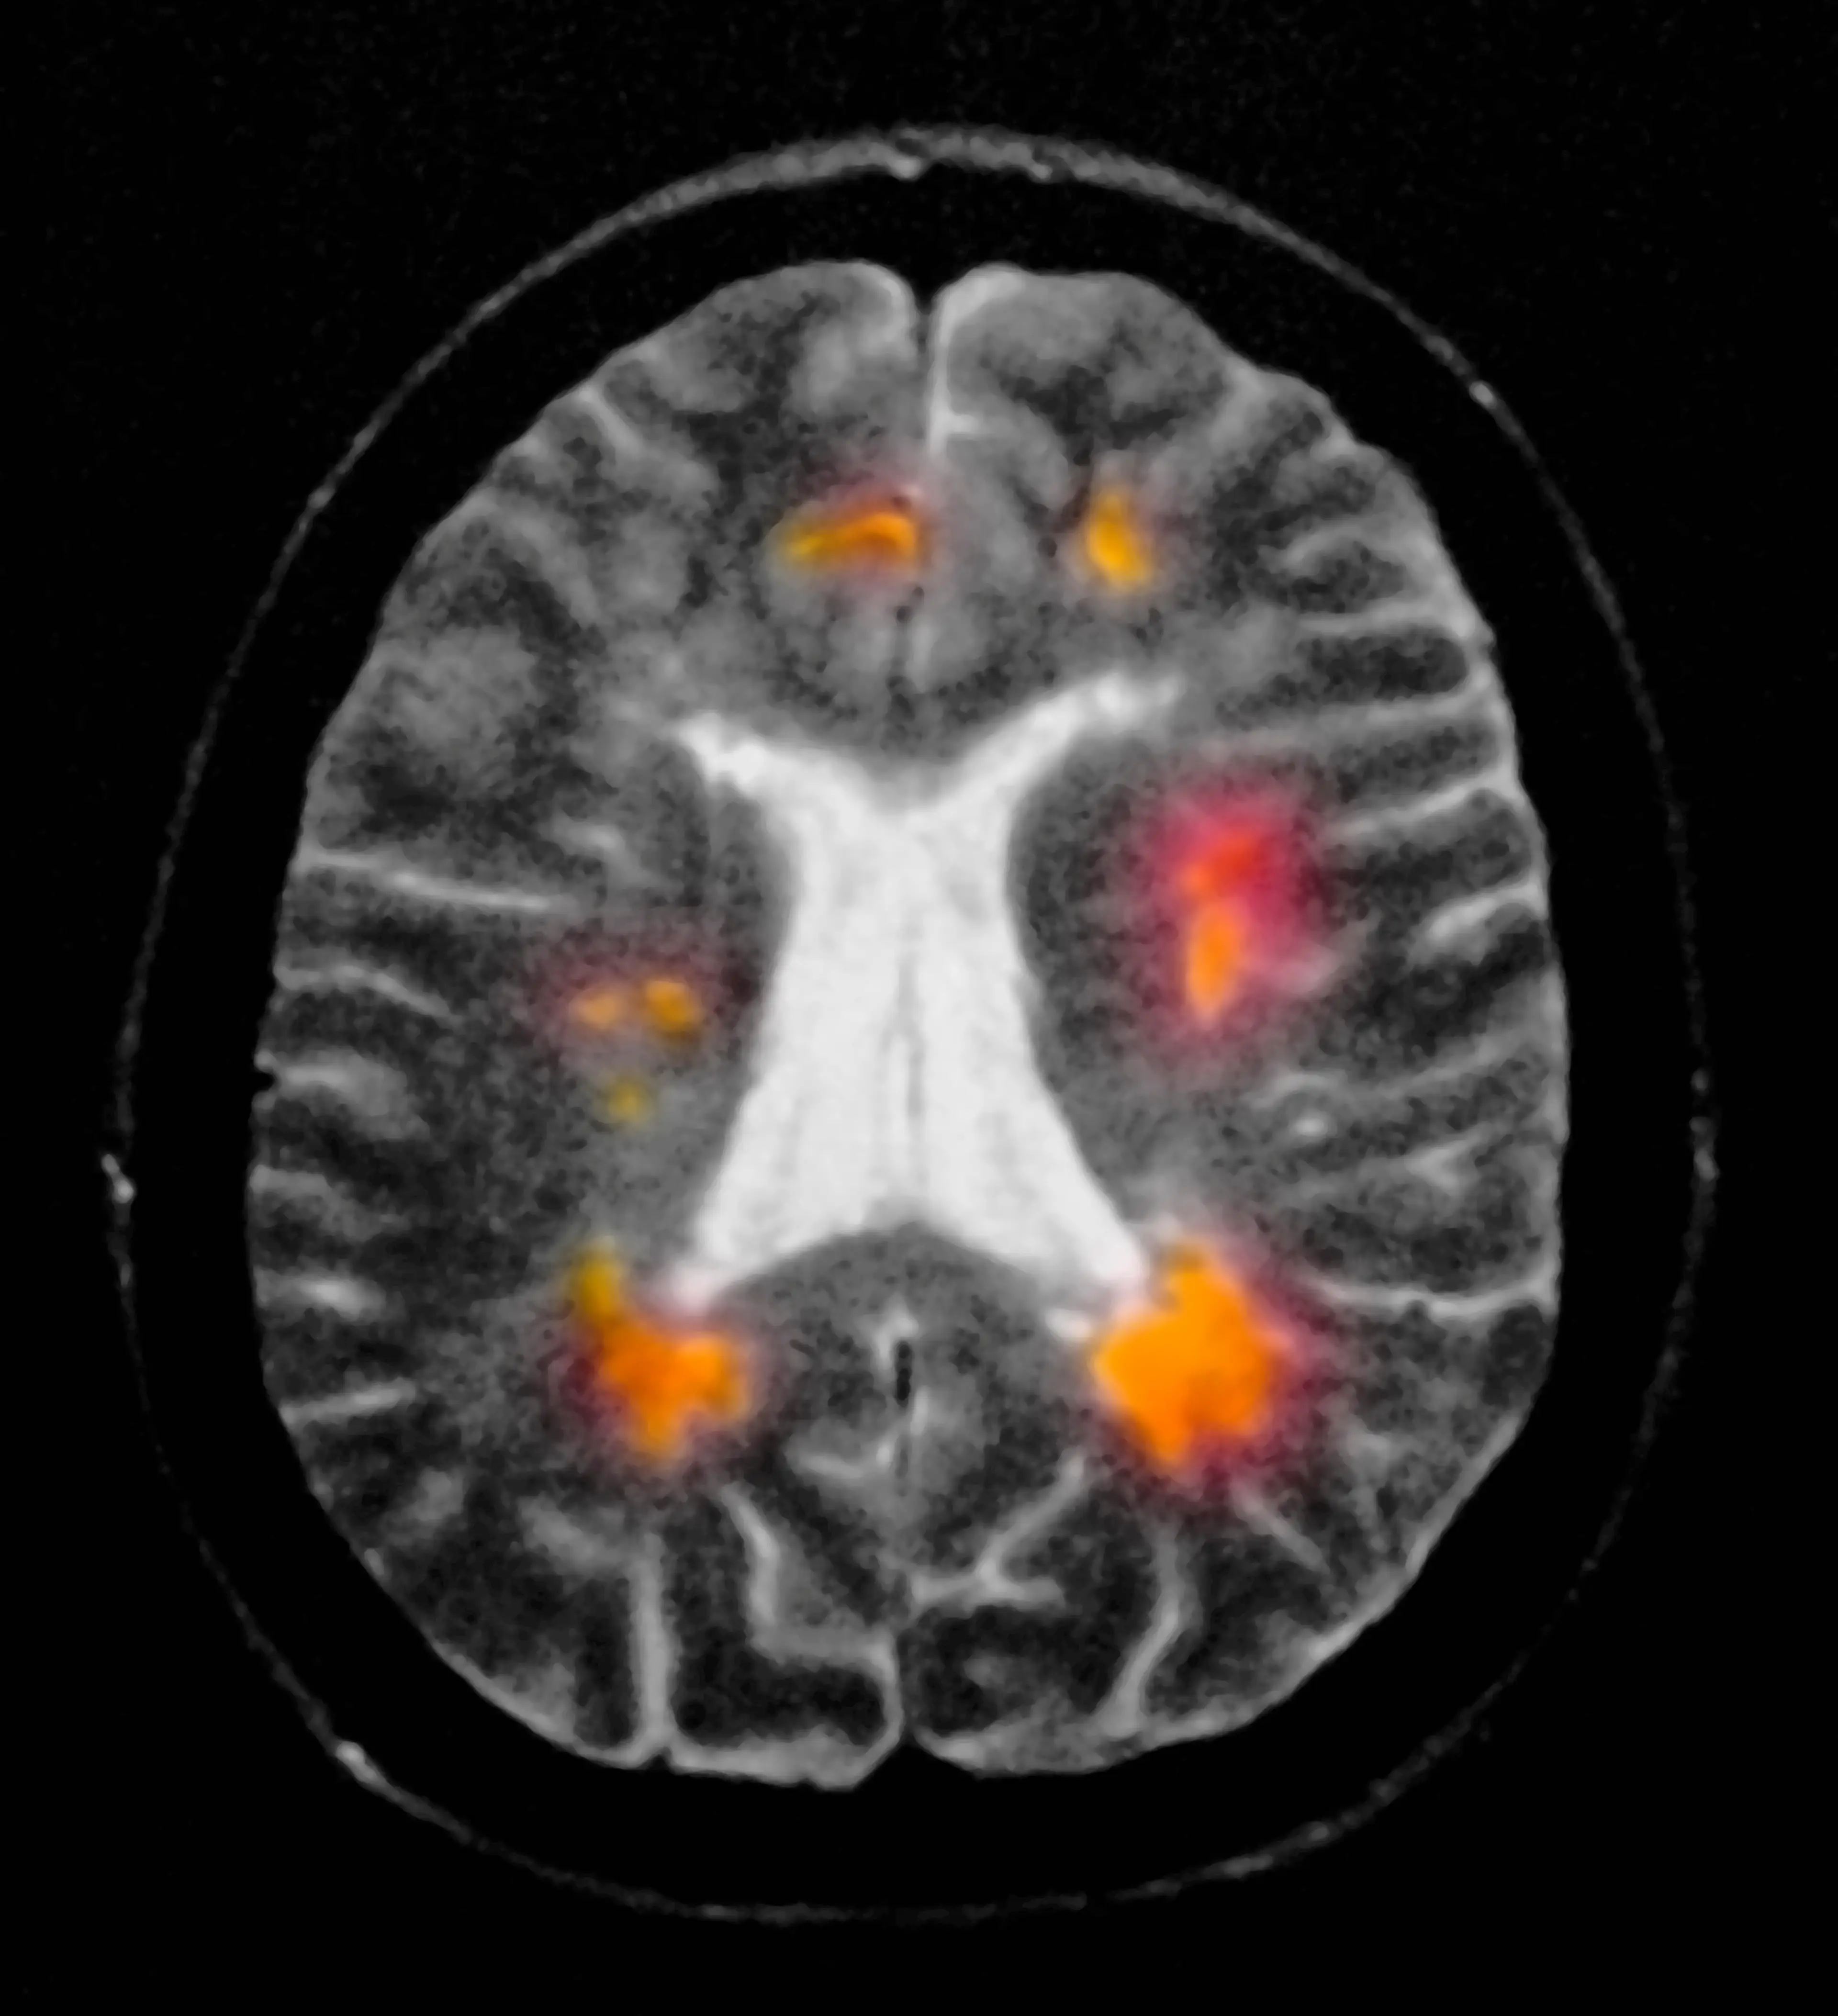

Multiple Sclerosis (MS) is a chronic, inflammatory, autoimmune disease which can develop in any part of the body.

MS attacks the central nervous system, meaning there can be damaged nerves that disguise as other symptoms/conditions.